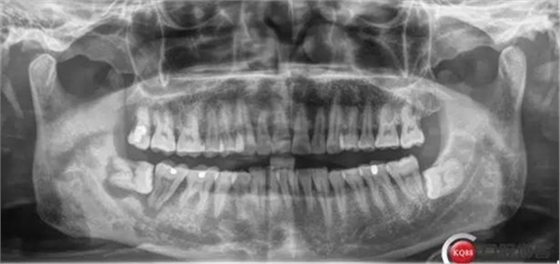

X線及CBCT檢查:47、48根尖周區(qū)大面積低密度影像,波及下牙槽神經(jīng)管,部分區(qū)域至神經(jīng)管以下。CBCT顯示神經(jīng)管走形于47根尖炎癥區(qū)下方(已侵犯)48炎癥區(qū)頰側(cè)(已侵犯)

術(shù)前CBCT分析